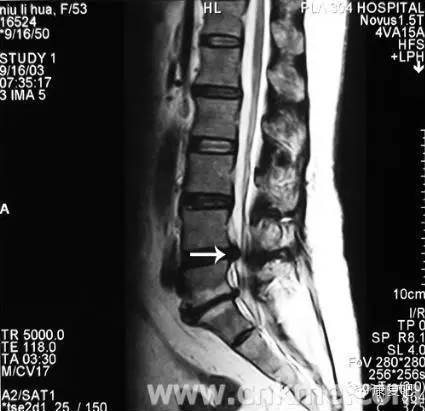

3、核磁共振摄影(MRI)

可显示出狭窄的部位(脊髓腔的狭窄)、椎间盘物质的突出进入脊髓腔、或受侵害之脊髓神经根。